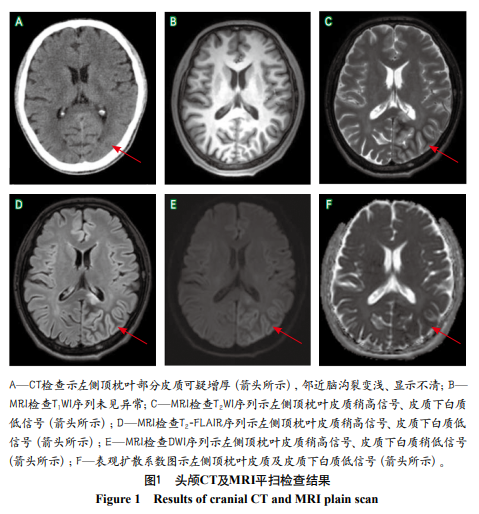

影像学检查

头颅MRI平扫示左侧顶枕叶皮质T2WI、T2-FLAIR及DWI序列呈稍高信号,表观扩散系数图呈低信号;皮质下白质T2WI、T2-FLAIR序列及表观扩散系数图呈低信号,DWI序列呈稍低信号(图1)。